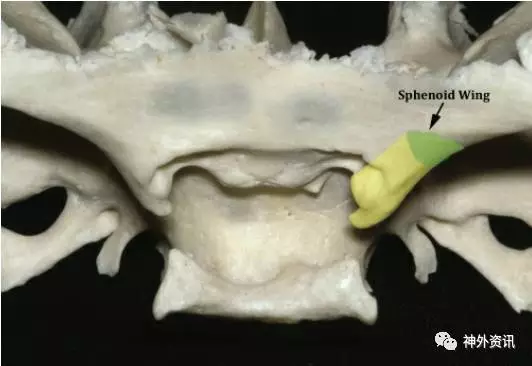

图3. 对于硬膜内前床突切除术,在硬膜外磨除蝶骨小翼并轮廓化眶上裂是扩大翼点开颅步骤的一部分(绿色)。因子,硬膜内前床突切除术的第一步,包括沿着蝶骨嵴离断前床突的外侧部,实际上是在硬膜外完成的。(感谢AL Rhoton, Jr教授对图片的授权)

图4. 步骤二,沿视神经管顶壁及额骨内侧(粉色)磨除,以离断前床突前部和内侧部;视神经减压也可在移位前床突而牵拉神经的过程中起到保护神经的作用。步骤三,在前床突内部行“蛋壳化”磨除,使其与前下方的视柱(绿色)相离断。这两步骤是在硬膜内进行的。(感谢AL Rhoton, Jr教授对图片的授权)